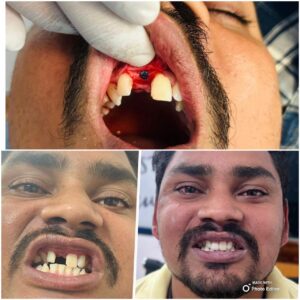

⦿ Implants (Full time Specialist available)

. Single tooth replacement

. Multiple teeth replacement

. Full mouth rehabilitation